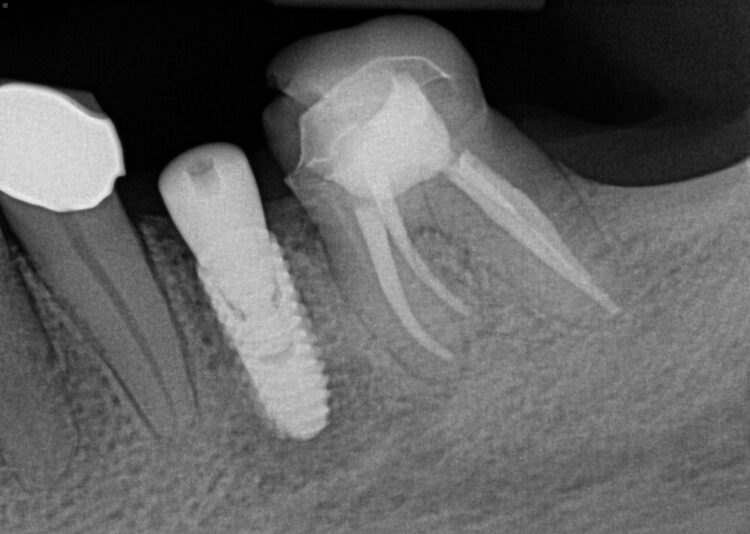

Hi, this implant was placed in June 2024. I have 3PAs (one from day of placement, one month later, and 9 month later). The intraoral picture of the soft tissue is from yesterday and tissue looks great… patient has no discomfort/pain either. She did have some discomfort between 2-3rd week after placement but subsided after taking antibiotics. On the one month xray, I may have missed the radioluency starting in apical 1/3.

Yesterday, I tapped the HA with the end of my mirror and wiggled the implant with no pain nor any perceptible movement. I am very suspicious, of course, about the radiolucency surrounding the apical 1/2 of the implant and am almost certain that the implant has failed (right?). I have removed failed implants at about 4 weeks (came out easily since still has not osseointegrated) but not at 9 months out…